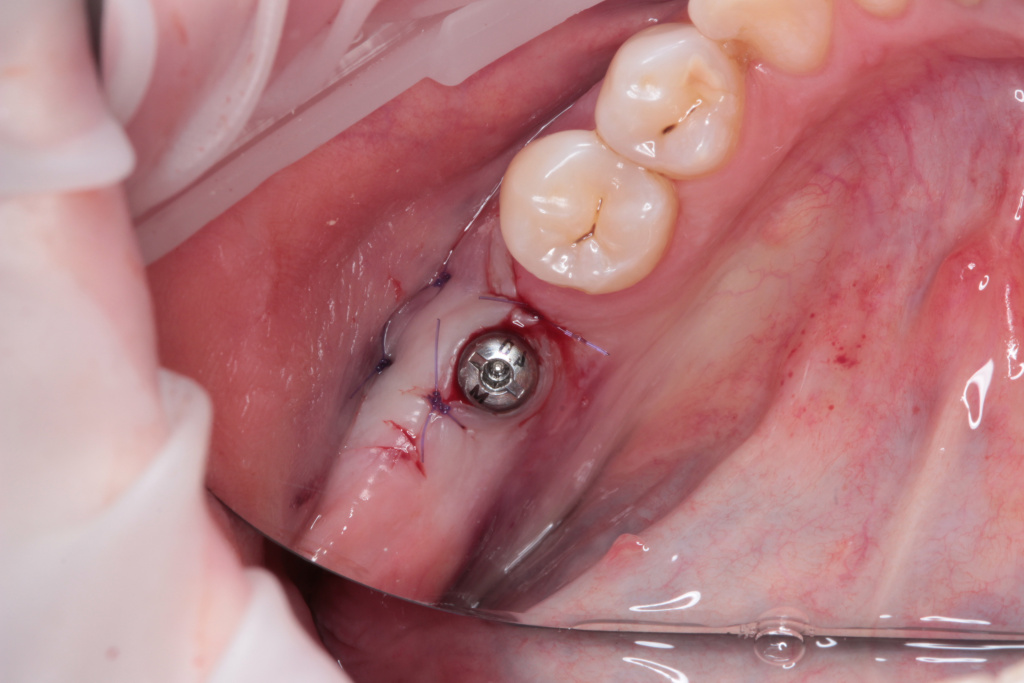

- Имплантация IMPRO

- Ушивание раны